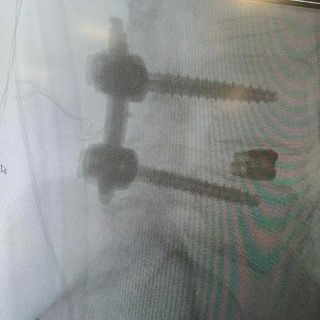

Starszy Asystent w Klinicznym Oddziale Neurochirurgicznym oraz Poradni Neurochirurgii Wojewódzkiego Szpitala Specjalistycznego im. św. Barbary nr 5 w Sosnowcu. Konsultant Kliniki Neurologii Szpitala Klinicznego nr 1 w Zabrzu. Absolwent Wydziału Lekarskiego Śląskiego Uniwersytetu Medycznego w Zabrzu. Staż podyplomowy odbył w latach 2010-2011 w Oddziale Neurochirurgii WSS nr 4 w Bytomiu. W 2018r. złożył egzamin specjalizacyjny po zakończeniu szkolenia w ramach rezydentury w WCM Opole. W 2019 roku uzyskał stopień doktora nauk medycznych. Specjalizuje się w kompleksowym leczeniu schorzeń kręgosłupa (dyskopatia, stenoza kanału kręgowego, kręgozmyk) oraz neuroonkologii. Szczególny zakres działań medycznych to nowoczesne, małoinwazyjne operacje kręgosłupa z wykorzystaniem technik endoskopowych (mikrodiscektomia - implanty rozprężalne), przezskórnych stabilizacji oraz mikrochirurgicznych dekompresji. Wykonuje procedury iniekcyjne; discoGEL, GelSTIX, kriolezje oraz blokady przeciwbólowe kręgosłupa odcinka szyjnego, lędźwiowo-krzyżowego a także stawów krzyżowo-biodrowych, które odgrywają istotną rolę w procesie diagnostyczno-leczniczym wielu zespołów bólowych. Na co dzień przeprowadza operacje w ramach kontraktu z NFZ. Członek Polskiego Towarzystwa Neurochirurgów oraz Polskiego Towarzystwa Chirurgii Kręgosłupa. Uczestnik wielu krajowych i zagranicznych kursów neurochirurgicznych, m.in. w Czechach, Słowacji, Niemczech, Włoszech, Danii, Austrii, Szwajcarii i USA. Autor licznych publikacji naukowych.

Zdjęcia i filmy